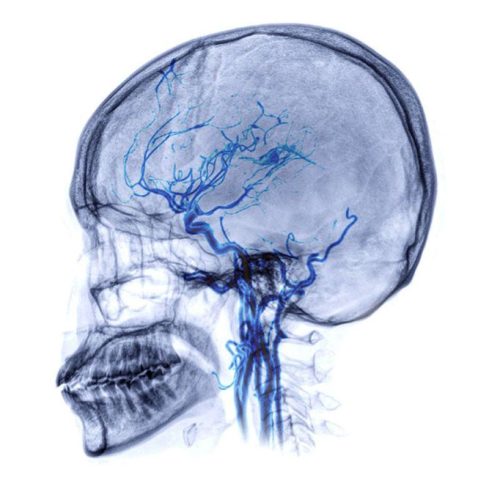

Η αυτόματη υπαραχνοειδής αιμορραγία εμφανίζεται στο διάστημα μεταξύ του εγκεφάλου και των μεμβρανών, που καλύπτουν τον εγκέφαλο. Συχνά αιτία είναι η ρήξη του εγκεφαλικού ανευρύσματος ή η ρήξη μίας αρτηριοφλεβικής δυσπλασίας. Η αυτόματηυπαραχνοειδής αιμορραγία αποτελεί το 3% των εγκεφαλικών επεισοδίων. - Αυτόματο υπο-επισκληρίδιο αιμάτωμα